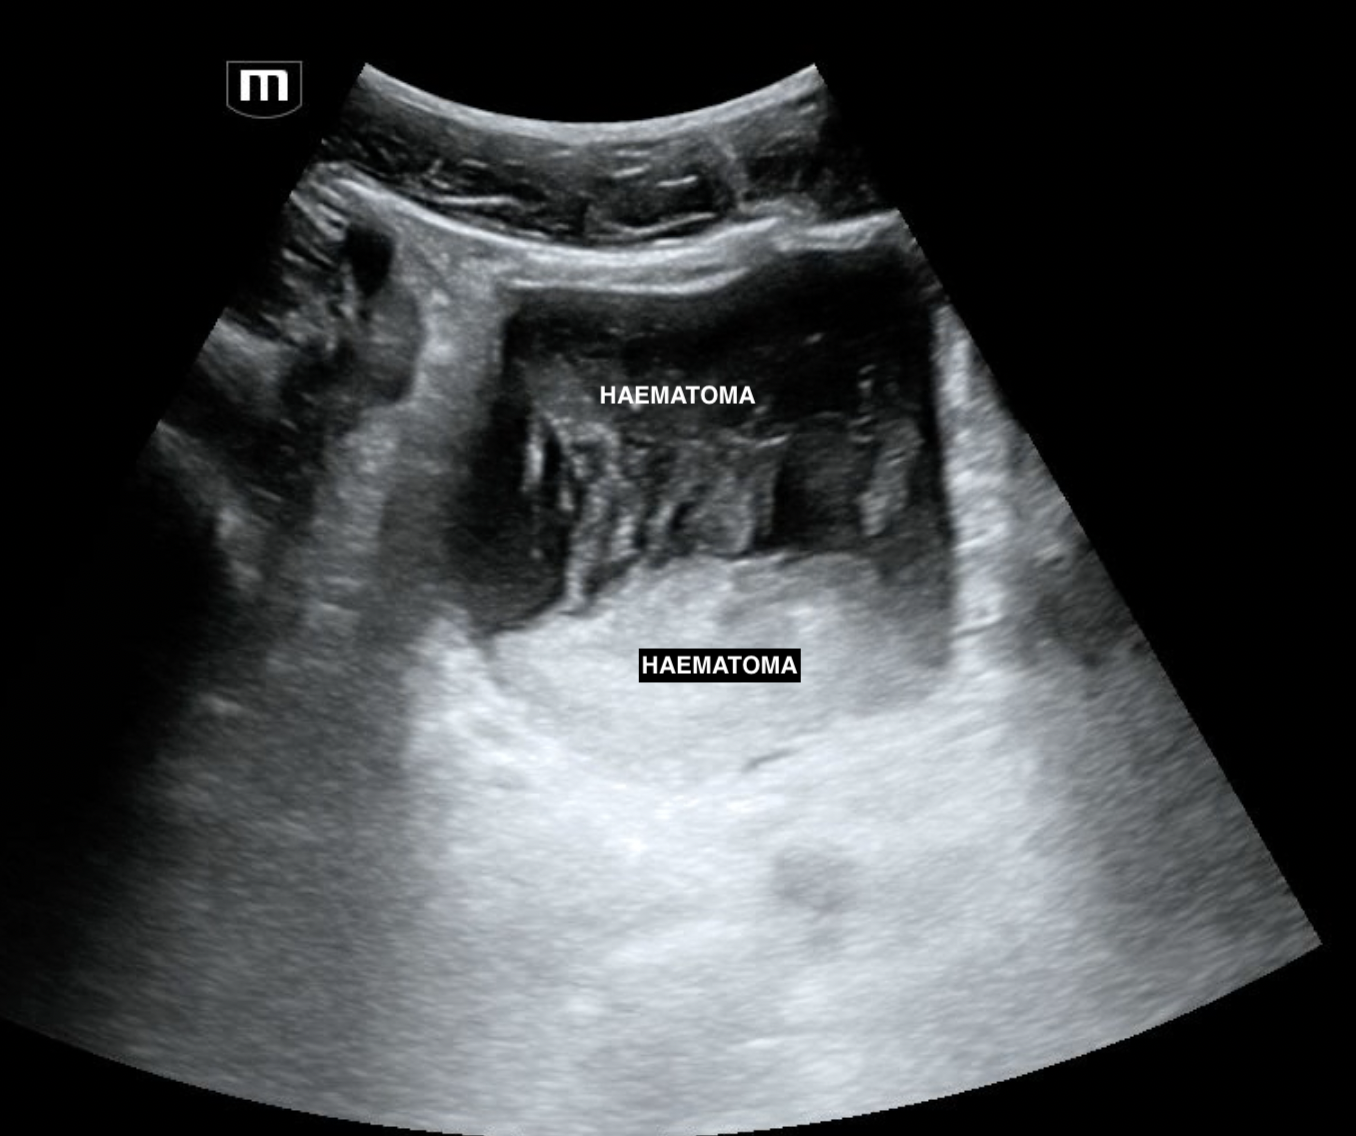

A FAST scan was done at the bedside:

pelvis trans (annotated below)

The bedside US allowed an expedited CT and trauma review. The CT request read "clot in bladder; renal pole injury"